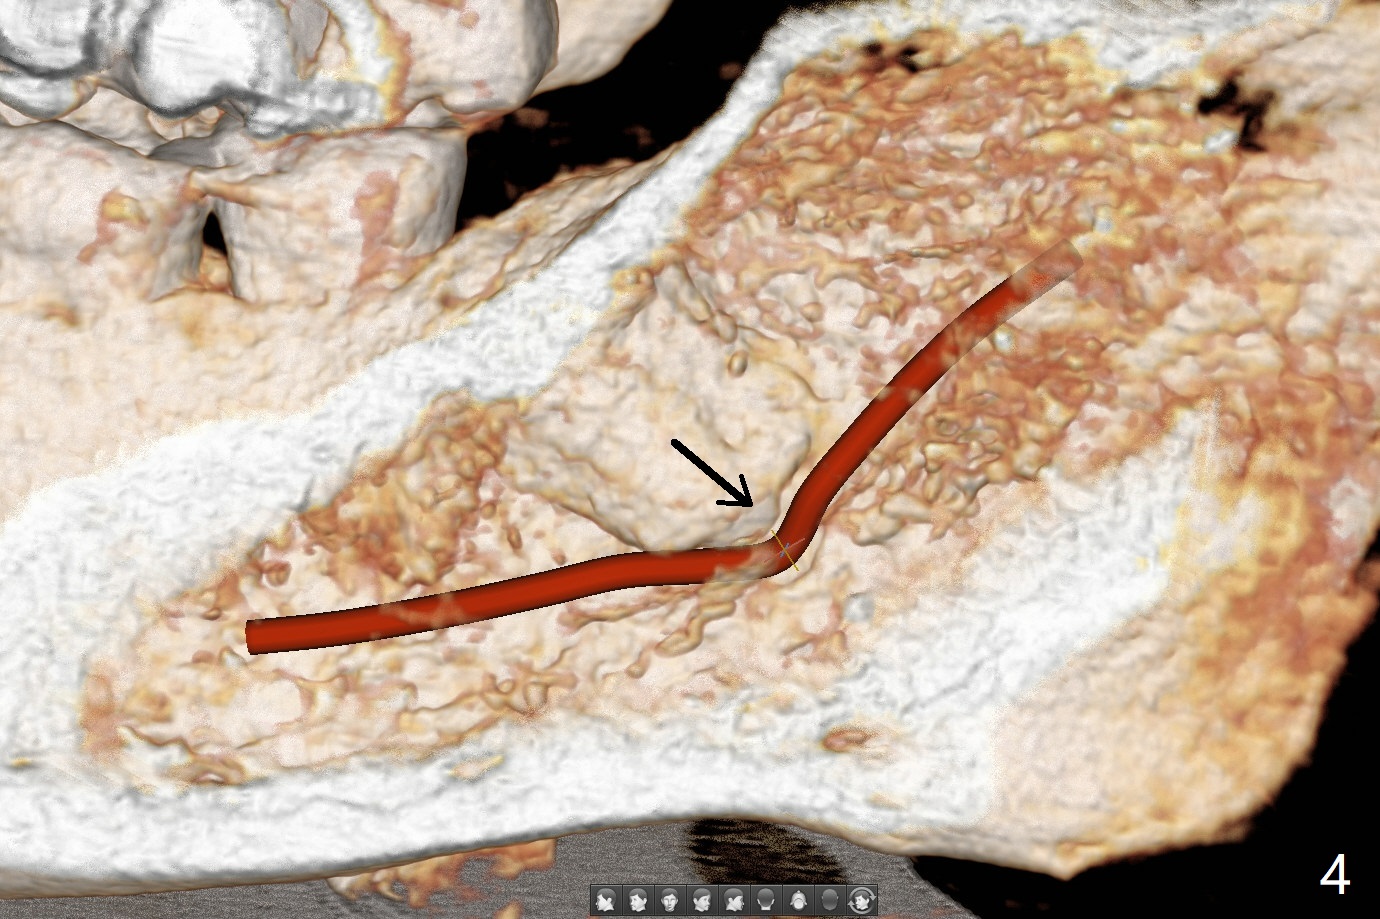

A 63-year-old woman wants to extract the tooth #18 with crack before termination of dental insurance (Fig.1). It is also possible to place an immediate implant in the septum (Fig.2). Socket shield is not needed because of the wide bone. If the implant is too close to the tooth #17, section the mesial portion of the latter (red dashed line), since removing the impacted tooth may risk injury to the Inferior Alveolar Canal (Fig.3,4). Draw one tube of blood for sticky bone.